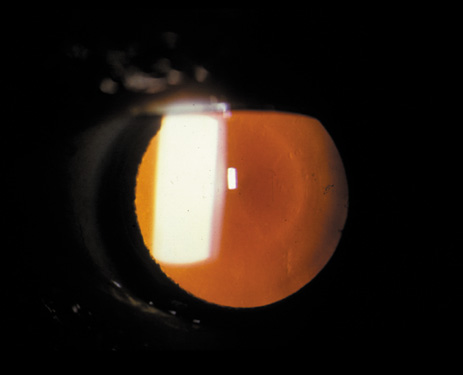

Nuclear cataracts tend to progress slowly. The refractive index of the lens changes as the nucleus progressively hardens, which usually results in increasing myopia.20,21 In some patients this is accompanied by optical distortion, especially of distant images, while near vision remains unaffected. A nuclear cataract is best seen with the narrow-beam direct illumination employed by the slit-lamp, which reveals the color and generalized haze or opalescence of the nucleus. In the early stages, the two halves (cotyledons) of the embryonic nucleus remain visible (Fig. 3). Later the entire nucleus appears as a homogeneous mass in contrast to the cortex (Fig. 4). Retroillumination may show the “oil droplet” effect (Fig. 5). Sometimes one may notice crystals in the lens nucleus (known as a Christmas tree cataract; Fig. 6A and B).

Fig. 4. Advanced nuclear cataract. Note the homogeneous nuclear opacity.